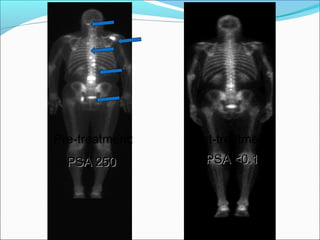

Antibody against CTLA-4 (ipilimumab) Beer et al. ASCO Abstract # 5004, 2008 26 patients with hormone refractory, end stage, metastatic prostate cancer treated with escalating doses (phase I) with or without radiation to a metastatic site. 6 men had greater than 50% decline in PSA. 2 men had PSA drop to zero. Side effects were diarrhea, liver inflammation and rash

Pre-treatment: Post-treatment: PSA 250 PSA <0.1